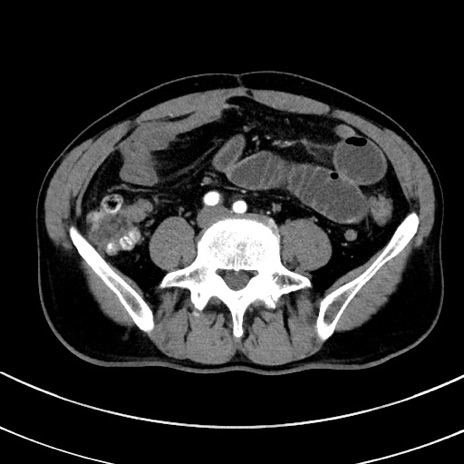

冠状断像

【症例】 60歳代男性

【主訴】 黒色吐物

【現病歴】 4日前から嘔気自覚、2日前の朝食後にも嘔気あり、自分で手で嘔吐反射起こし嘔吐したところ血が混ざっていたため受診。

【既往歴】 5年前汎発性腹膜炎を伴う急性虫垂炎で手術、高血圧、前立腺肥大症、高脂血症

【身体所見】 腹部正中に手術癩痕あり 腹部平坦・軟圧痛なし膨満感あり

【データ】WBC 8400、CRP 4.54